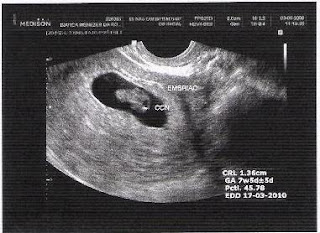

Primeira Ultra-Sonografia !!!

Realizada: 03/08/2009

Gestação: 7 semanas e 5 dias

Presença do embrião: 1,36 cm

Batimentos cardíacos: 164 bpm